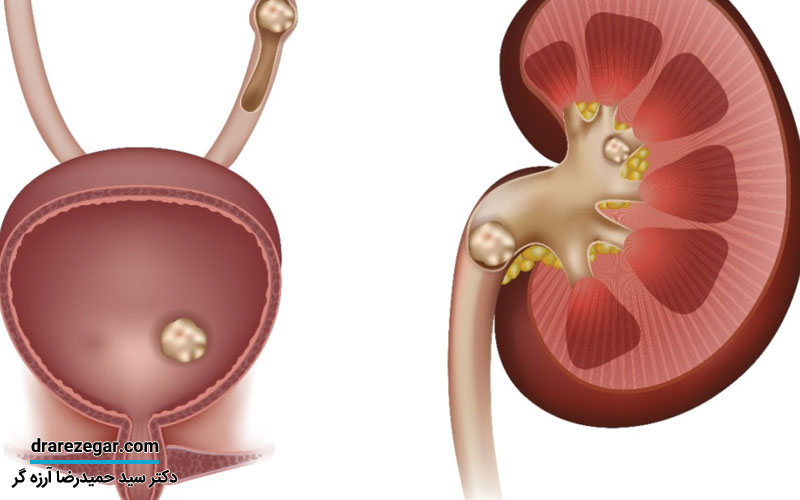

سنگ کلیه و سنگ حالب، مشکلی است که بسیاری از مردم به آن دچار هستند. احتمالاً همه ما در خانواده هایمان، فردی را می شناسیم که با این بیماری، درگیر است. اما چگونه می توان از ابتلا به این مشکل، جلوگیری کرد؟ آیا راهی قطعی برای پیشگیری از ساخت سنگ کلیه و سنگ حالب، وجود دارد؟ در ادامه این مطلب، قصد داریم تا به بررسی این دو پرسش و یافتن پاسخی برای آن ها، بپردازیم.

چه مشکلاتی خطر ابتلا به سنگ کلیه و سنگ حالب را افزایش می دهند؟

از جمله مشکلاتی که خطر ابتلا به سنگ کلیه و سنگ حالب را افزایش می دهند، می توان به موارد زیر اشاره کرد:

• انسداد مجاری ادراری